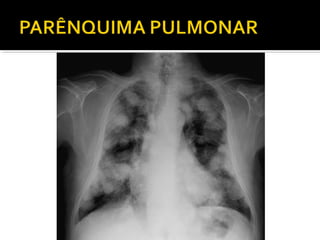

Este documento fornece parâmetros técnicos para realizar uma radiografia de tórax, incluindo posicionamento correto do paciente, dose adequada de radiação e estruturas anatômicas a serem avaliadas, como coração, pulmões, pleura, diafragma e ossos do tórax.